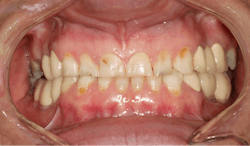

After the first phase consisting of caries control and periodontal treatment, the patient received soft- and hard-tissue crown lengthening by laser (figure 5). After an eight-week healing period, full-mouth cosmetic restorations were placed, which included full- and three-quarter-coverage e.max crowns and zirconia bridges (figures 6–7).

Following therapy, the patient was seen every three months for hygiene recare and to evaluate the status of caries and gingival inflammation. CariFree CTx4 Gel, home-administered sodium fluoride trays, and interproximal irrigators were given to the patient to increase resistance to caries. Oral hygiene instruction was an integral part of the recare visits and proved to be valuable in maintaining the patient’s results two-and-a-half years later (figure 8).